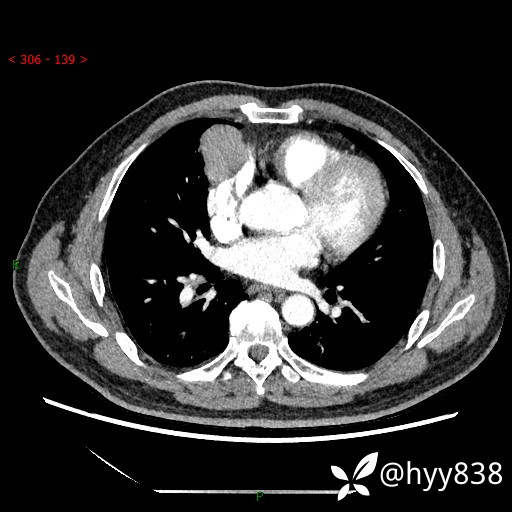

胸部CT平扫

动脉期+静脉期

各期CT值